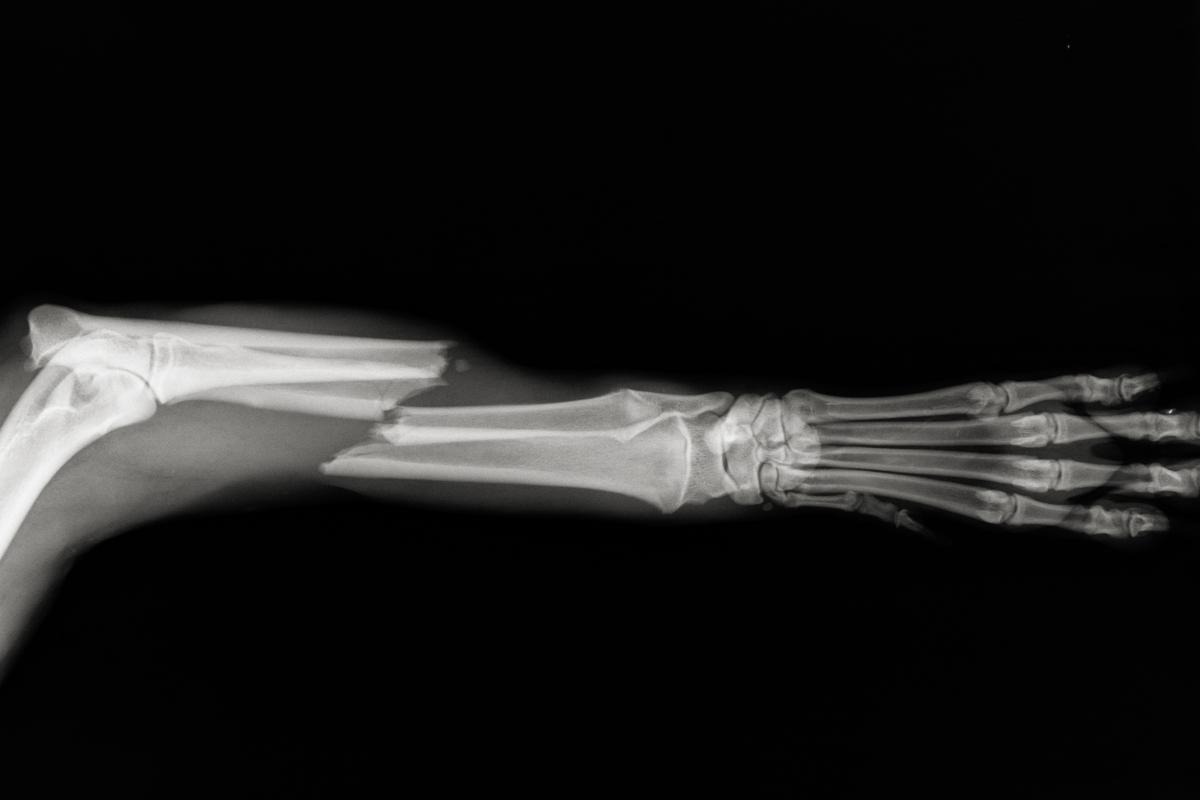

Otra afección que produce mucho dolor en los perros y que puede ser la causa de que tu perro grite de dolor de repente son las fracturas. Las fracturas consisten en la rotura de uno o más huesos en el animal como consecuencia de una gran fuerza sobre los mismos. También se producen por peleas entre perros, caídas, accidentes o cualquier traumatismo que ejerza la fuerza suficiente para fracturar el hueso. Generalmente, los perros afectados por fracturas chillan cuando los intentas coger o tocar en la zona fracturada.

Los perros se pueden fracturar muchos de los huesos que componen su esqueleto y no solo los de las patas, sino que la pelvis, las costillas o la mandíbula también pueden romperse. El dolor es el primer síntoma asociado a las fracturas y se acompaña rápidamente de un proceso inflamatorio. En el caso de las fracturas mandibulares, el perro podrá manifestar una pérdida de apetito; en el caso de la pelvis, puede manifestar cojeras o parálisis de la parte posterior; y en el caso de las fracturas de las costillas, podrán manifestar dificultad respiratoria. Te recomendamos consultar estos artículos: